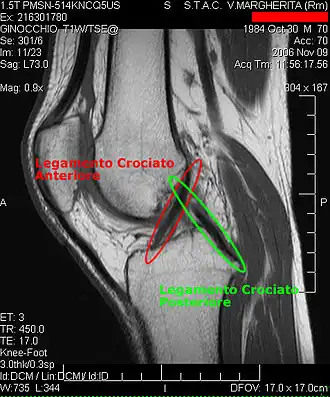

De voor-achterwaartse stabiliteit in het kniegewricht wordt vooral bereikt door kruislingse banden (de kruisbanden/ligamenta cruciformia) die boven- en onderbeen verbinden. De zijwaartse stabiliteit wordt gewaarborgd door de ligamenta collateralia. Een soepel scharnieren van het bovenbeen ten opzichte van het onderbeen wordt bereikt doordat de knie omvat is in een kapsel en door de aanwezigheid van kraakbeenschijven tussen de scharnierende botdelen (de menisci). Stabiliteit (passief) wordt bereikt door de kniebanden en kruisbanden en (actief) door de bovenbeenspieren.

- De kruisbanden in de knie. Deze voorkomen verschuiving van het boven en onderbeen, voorwaarts of achterwaarts.